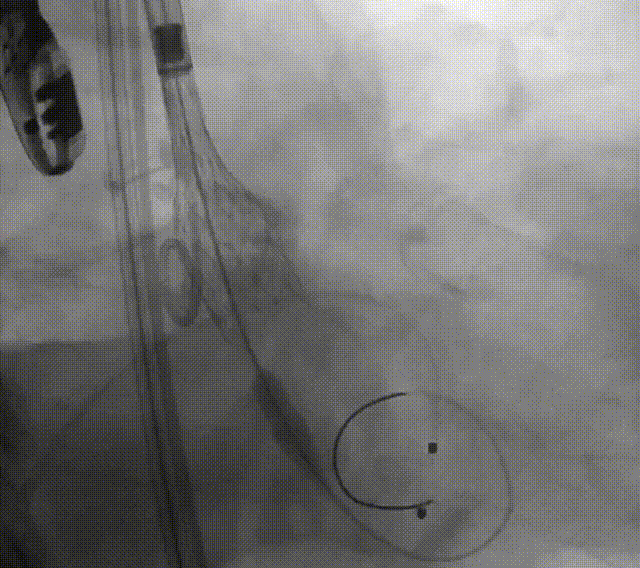

造影评估

跨瓣压差

术前120mmHg

释放后4mmHg

超声评估

后扩否?

瓣膜是否有弹出风险?如何避免?

再次与根部造影对比

通过与术前主动脉根部造影的对比,确认两侧深度平均但较临界,可谨慎操作下尝试球囊后扩张以使流入端瓣架充分膨胀贴合自体瓣环,减少瓣周漏。

23mm Z-Med后扩张

最终结果